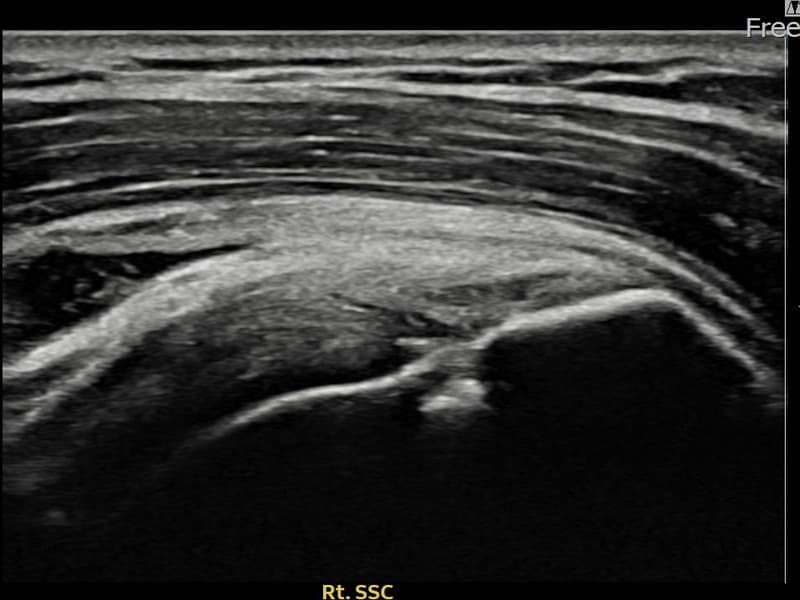

施術後

術前超音波にて右 棘下筋腱 関節面側部分断裂・右肩棘下筋腱のエコー不連続と腱欠損(7mm × 3mm (腱厚の約32%欠損))を確認。術後超音波では断裂部位が再生組織で充填され、腱の連続性回復とエコーパターンの正常化が確認されました。

持続する右肩痛で来院された患者様です。超音波検査にて右 棘下筋腱 関節面側部分断裂(欠損:7mm × 3mm (腱厚の約32%欠損))を確認し、超音波ガイド下で非手術的縫縮術を施行しました。術後は約4〜6週間のブレース装着の後、段階的なリハビリプログラムを実施。経過超音波で腱の連続性回復を確認し、患者様は無事に日常生活へ復帰されました。